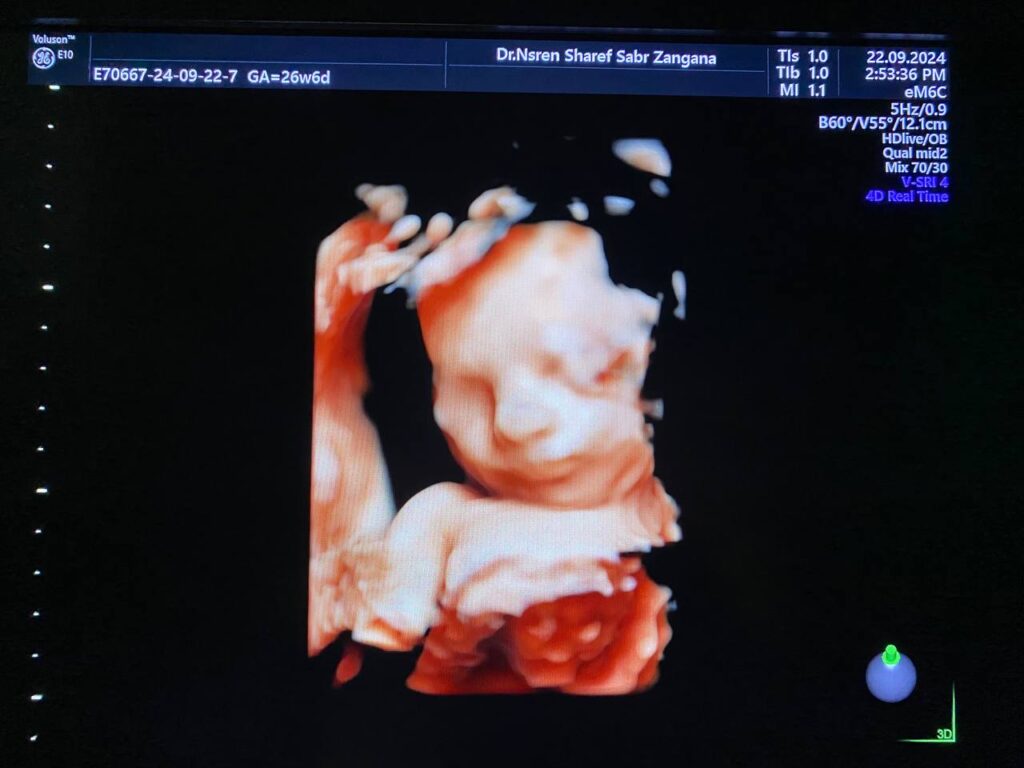

Face of fetus 26 weeks gestational age